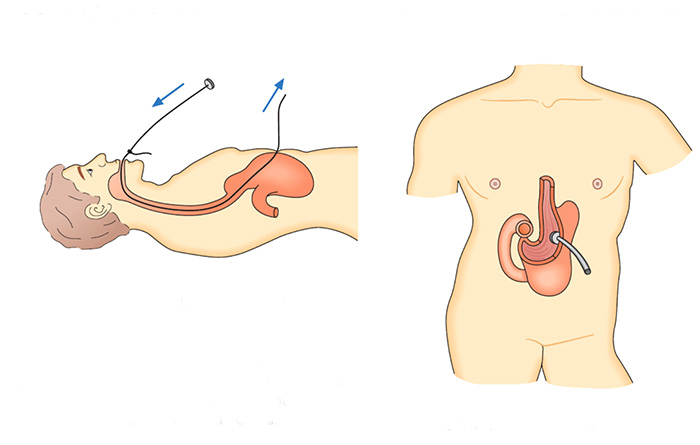

Gastrostomia endoscópica é a colocação de um tubo de alimentação diretamente para o estômago, através da parede abdominal.

Quando ela é usada?

Este procedimento pode ser feito para alimentar você, se você não consegue comer normalmente. Por exemplo, você pode precisar de uma gastrostomia se:

- Não puder engolir por algum problema como câncer de boca ou garganta, ou acidente vascular cerebral (AVC).

- Outros problemas para engolir (problemas de deglutição)

- Em alguns tratamentos médicos, como quimioterapia ou radioterapia, que são temporários mas as vezes tornam difícil você comer o suficiente para obter uma boa nutrição.

- Casos de desnutrição severa.

Alguns tubos de alimentação temporários são passados através do nariz até o estômago, são as chamadas sondas nasoenterais. Um tubo de gastrotomia é normalmente colocado para permitir a remoção de uma sonda nasoenteral, de modo que a alimentação possa continuar com maior conforto e por tempo mais prolongado.

O que acontece durante o procedimento?

Para a gastrostomia endoscópica percutânea, você receberá um sedativo e um anestésico local para mantê-lo sem sentir dor. O médico irá introduzir um endoscópio através de sua boca até o seu estômago. Um endoscópio é um tubo fino e flexível com uma pequena câmera. Ele permite que o médico olhe para o interior de seu estômago durante o procedimento.

O seu médico irá encher o estômago com ar para torná-lo maior e empurrar a parede do estômago mais perto da parede abdominal. O médico irá guiar uma agulha e fio através de sua pele e parede abdominal até o seu estômago. O endoscópio permite ao médico ver e capturar o fio dentro do estômago.

O fio é então puxado de volta pela boca. Um tubo de plástico é ligada ao fio e puxado através da boca ao longo do percurso até o estômago.

O médico irá fixar o tubo de dentro do estômago e na sua pele. O pedaço curto do tubo de borracha visível através da parede abdominal é facilmente coberto com a roupa.